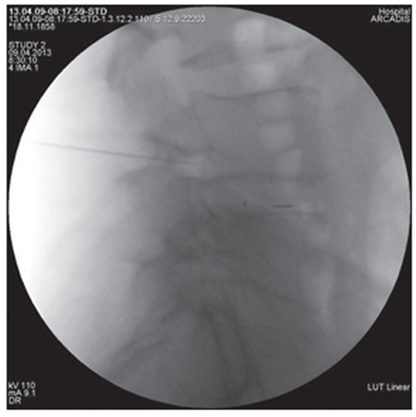

Figure 4. Intraoperative X-ray of the lumbar spine in frontal projection. Epidurography and possible routes of contrast agent distribution |